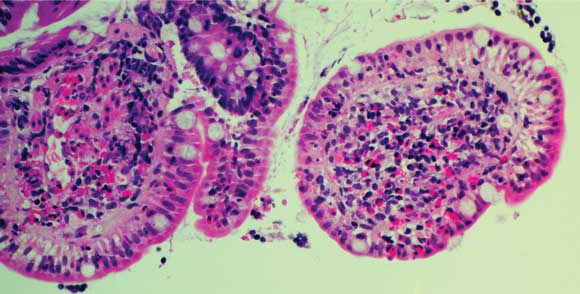

Colonoscopy revealed mild terminal ileitis. Biopsies of the affected area showed an eosinophilic infiltrate in the lamina propria and submucosa, but intact surface epithelium. Occasional adult worms measuring about 70 μm wide at the midbody were seen on the luminal surface (Box 1A and B), and were initially identified as Enterobius vermicularis. He was treated with two 100 mg doses of mebendazole 1 week apart. However, he re-presented 3 weeks later with no improvement in his symptoms and a persistent eosinophilia (1.4 × 109/L).

On this occasion, faecal concentration was performed using formalin-ethyl acetate, and parasite eggs were detected on iodine wet mount (Box 1C). These were initially misidentified as hookworm eggs, but subsequent review confirmed that they were eggs of Trichostrongylus sp. The parasites seen on terminal ileal biopsy were also reviewed. Their morphology and dimensions (70 μm-wide body) were found to be consistent with adult Trichostrongylus.1

1 Samples from Patient 1

A: Biopsy of terminal ileum showing eosinophilic infiltrate in the lamina propria and submucosa, with a parasite on the luminal surface. B: Enlargement of parasite. C: Iodine wet mount of faecal specimen showing a Trichostrongylus egg. |